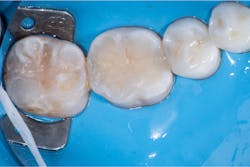

In this case, lateral access was achieved by the preparation of the adjacent teeth as part of the proposed treatment plan. Early caries lesions that are noted on radiographs that are not accessible in cases such as this one can be accessed by placing an orthodontic spacer. This patient was restored with direct composite bonding (figure 5) and these restorations have proven to have a favorable long-term outcome (figure 6).